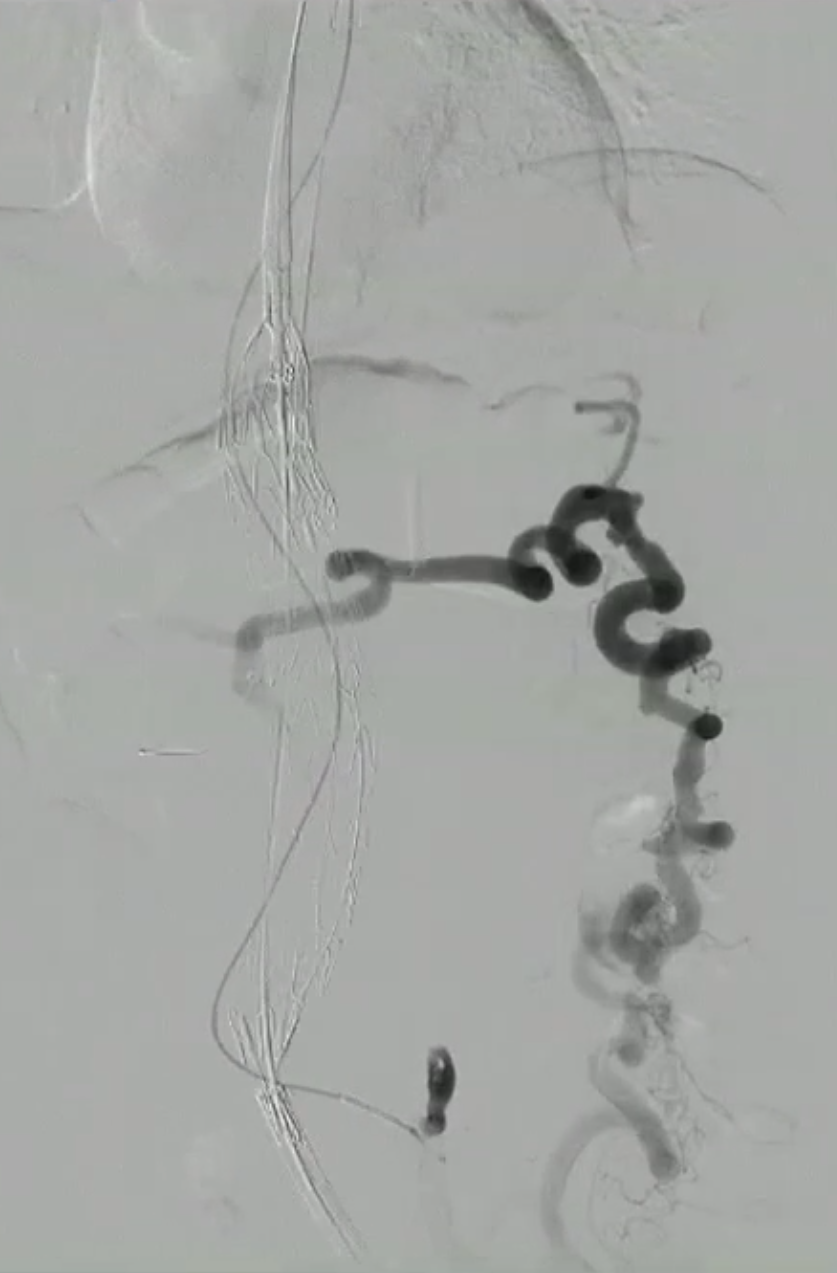

病例:包膜下血肿

术后第二天:腹胀,血常规:血色素10.4g,肾功能指标稍高

术后第三天:血压下降85/50mmHg,心率增快,胸闷加重。血常规示血色素7g,肾功能异常。CT右肾包膜血肿,后腹膜血肿